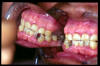

CM Edentulismo parcial, restos radiculares, caries y placa bacteriana